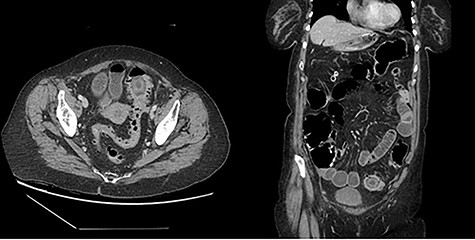

The first patient is a 77-year-old female who presented to the emergency room with a 5-day history of nausea, vomiting, diarrhea and frequent belching. She had a past medical history significant for two episodes of diverticulitis treated non-operatively. She had never undergone abdominal surgery and she had no prior colonoscopy. She was afebrile and hemodynamically stable on evaluation. Her abdominal exam revealed mild distention without tenderness or peritoneal signs. No palpable masses were present on rectal exam. Her labs were remarkable for a mild leukocytosis of 12.4 thou/cmm. She underwent CT imaging of her abdomen and pelvis with oral contrast, which indicated the presence of a gallstone impacted in the proximal sigmoid colon with no contrast passing beyond this location; associated mild small bowel distention and pneumobilia suggested a cholecystoduodenal fistula (Fig. 1).